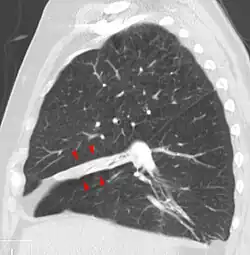

Rounded atelectasis

Rounded atelectasis (folded lung or Blesovsky syndrome[24]) is often mistaken for lung cancer on imaging. The most common current theory for rounded atelectasis is that local pleural irritation leads to thickening and shrinkage of the pleura which causes the adjacent lung to shrink with it.[25] The outer portion of the lung slowly collapses as a result of scarring and shrinkage of the membrane layers covering the lungs (pleura), which would show as visceral pleural thickening and entrapment of lung tissue. This produces a rounded appearance on X-ray that doctors may mistake for a tumor. Rounded atelectasis is usually a complication of asbestos-induced disease of the pleura, but it may also result from other types of chronic scarring and thickening of the pleura.[25]